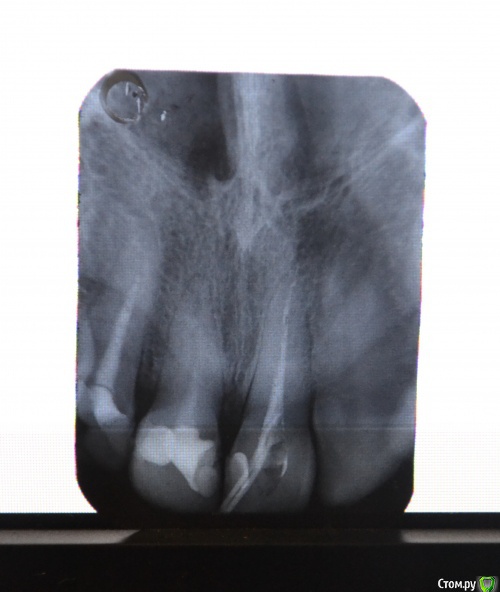

Llllll Опубликовано 28 июля, 2015 Автор Поделиться Опубликовано 28 июля, 2015 Перефотографировала, но не знаю какой снимок лучше, поэтому скинула все которые вышли) В среду канал сразу после этого рентгена запломбировали, к субботе начал очень сильно болеть, терпела, сегодня пошла на прием, открыли канал, но не скажу что стало лучше, может немножко. Боли пульсирующие, около носа, где верхушка зуба. Врач сказала что не знает что дальше делать( И почему оно болит( Ссылка на комментарий

Zlata-doctor Опубликовано 29 июля, 2015 Поделиться Опубликовано 29 июля, 2015 если вы не хотите потерять этот зуб ( а также и два соседних , которые тоже нуждаются в лечении), советую вам найти стоматолога, использующего современные протоколы эндодонтического лечения. Ни один из трех представленных на этих ужасных снимках зубов не пролечен как следует. Линкомицин, гидрокортизон, фонофорез итд -бегите оттуда. Извините за резкий тон, я Вам очень сочувствую. 1 Ссылка на комментарий

St. Опубликовано 11 августа, 2015 Поделиться Опубликовано 11 августа, 2015 По снимку все три зуба нуждаются в качественном лечении. Причем вполне возможно, что какие-то ощущения дает ещё соседний центральный зуб. Кусочка инструмента не увидела.Я понимаю, что найти хорошего стоматолога совсем не просто. Как минимум имейте ввиду, что оставлять зуб открытым - это плохо, колоть в десну антибиотики и гормоны, и выводить много-много чего-то там за пределы зуба - тоже не очень. 2 Ссылка на комментарий

Гарриевич Опубликовано 11 августа, 2015 Поделиться Опубликовано 11 августа, 2015 на этом снимке нет выраженных признаков периодонтита, но это не значит что его нет Ссылка на комментарий